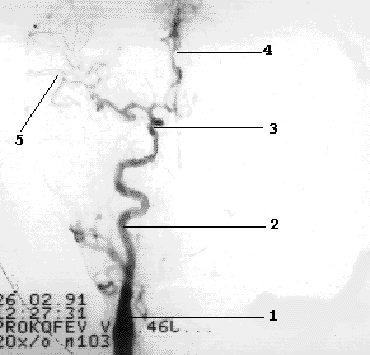

Наружная сонная артерия имеет короткий ствол, делясь на ряд ветвей, что легко позволяет отличить ее от ВСА. Насчитывают девять ветвей НСА, ряд из которых (терминальные ветви лицевой, поверхностной височной и верхнечелюстной артерий) анастомозируют с конечными ветвями глазничной артерии (первая интракраниальная ветвь ВСА) (Рис 1.4).

Рис 1.4.

Схема глазничного анастомоза.

1- ОСА, 2- НСА, 3- лицевая артерия, 4- ПВА, 5- ГА, 6-глазничный анастомоз.